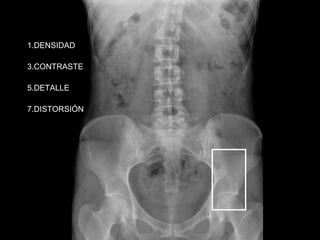

DENSIDAD CONTRASTE DETALLE DISTORSIÓN